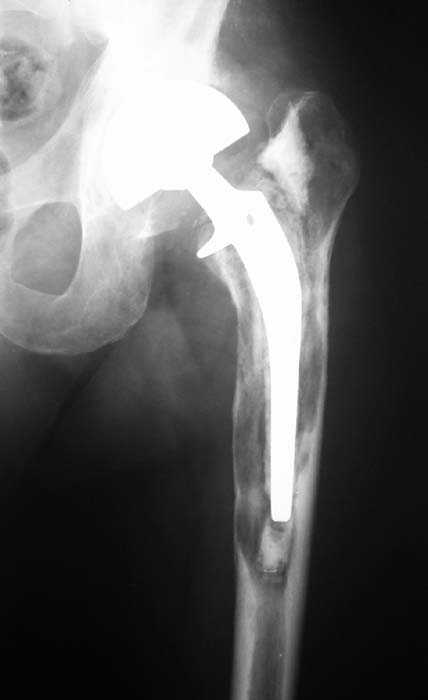

Мужчина, 39 лет.По поводу двустороннего асептического некроза головок бедренных костей последовательно выполнено тотальное эндопроезирование левого (1998 г), затем правого (1999 г) тазобедренных суставов.

22/10/04

С 2001 г отмечает нарастающие боли в левом бедре. Предполагается удаление протеза, удаление цемена из канала бедра, пластика дефекта бедренной кости.

Нет никакого смысла делать операцию в два этапа. С чашкой все понятно - стандартный подход с установкой пресс-фит компонента. На бедре имеет

место перипротезный перелом В3 типа - т.е. перелом вокруг ножки с ее нестабильностью на фоне выраженного остеолиза. Решение - доступ к каналу

через перелом с удалением самой ножки, костного цемента и рубцовых тканей. Установка ножки дистальной фиксации (типа Solution), длину ножки

надо определить по шаблону. Минимальный контакт ножки с интактной костью - 6-8 см. Фрагменты проксмального отдела собираются на ножке

эндопротеза, дефекты костной ткани заполняются чипсами (аллографт) и фиксируются кортикальными аллографтами, уложенными дополнительно по типу

"вязанки хвороста" серкляжом. Мы имеем 8 или 10 подобных наблюдений и результатами довольны.